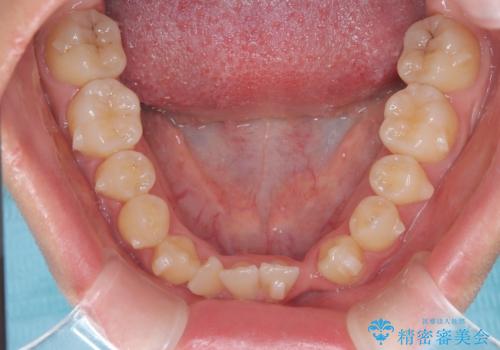

- 他院でインビザライン矯正を行っていたものの、通院先の閉院により治療が継続できなくなったとのことで来院されました。

診査の結果、すでに下顎前歯の抜歯が行われていましたが、マウスピースの適合が著しく悪くなっており、歯が計画通りに動いていない状態でした。また、歯を支える骨の厚みや歯肉の薄さを考慮すると、このままマウスピースによる傾斜移動を続けるのは歯肉退縮(歯茎が下がること)のリスクが非常に高いと判断。

安全かつ確実に抜歯スペースを閉じ、咬み合わせを完成させるため、マウスピースから**ワイヤー矯正(マルチブラケット装置)**へ切り替えるリカバリープランを提案しました。